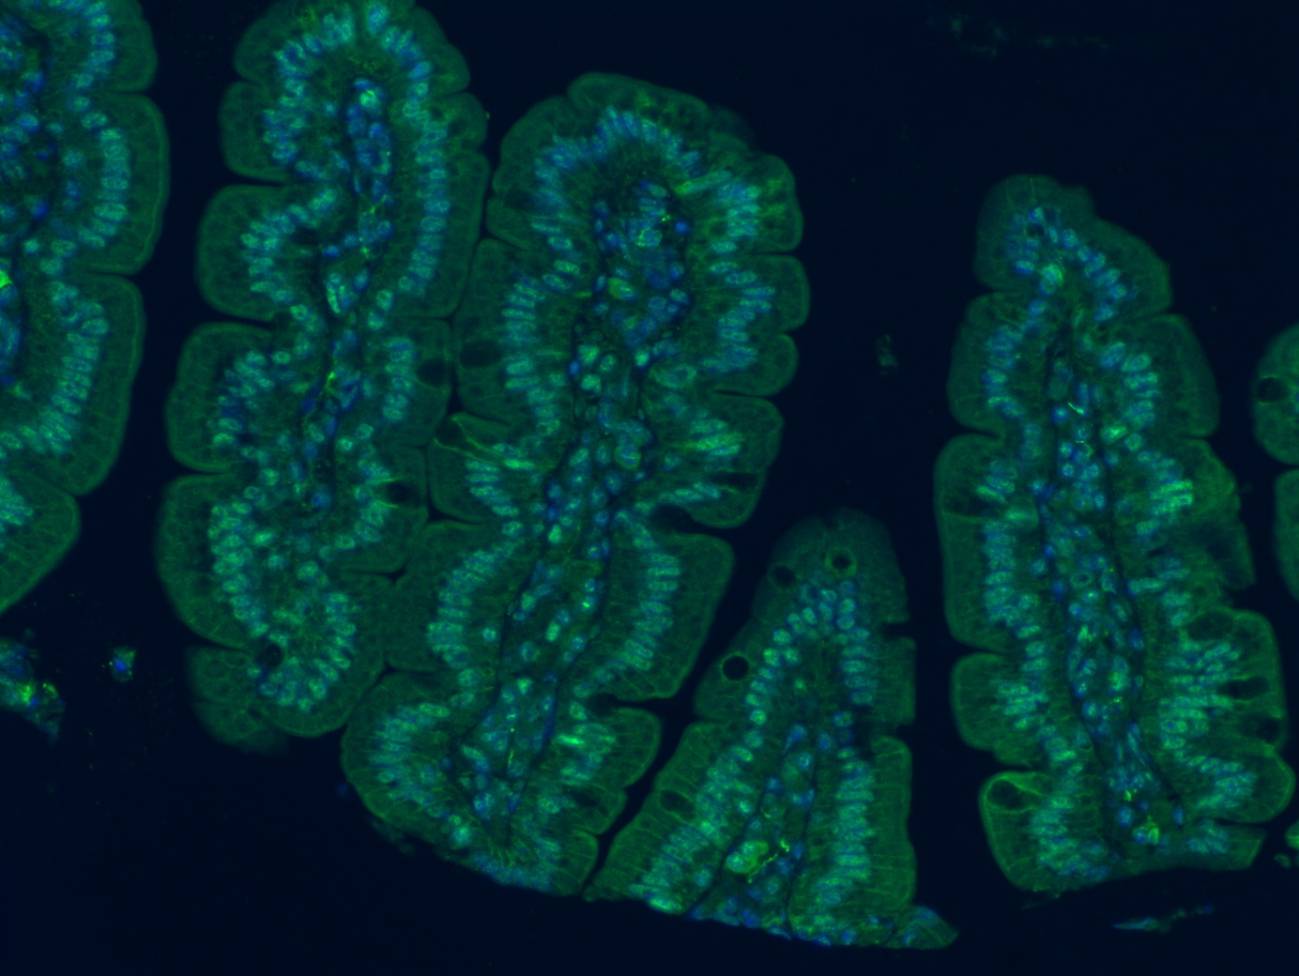

Para comprobar su teoría de que la microbiota intestinal influye en el envejecimiento cerebral, los investigadores alojaron a ratones jóvenes (de 2 meses) junto con ratones viejos (de 18 meses).

Al vivir y defecar juntos, los ratones jóvenes quedaron expuestos a la microbiota intestinal de los ratones viejos y viceversa.

Tras pasar un mes en convivencia, los investigadores examinaron la composición de los microbiomas de los animales viejos y jóvenes. Descubrieron que compartir espacio hizo que los microbiomas de los jóvenes se asemejaran más a los de los animales mayores.

El equipo observó que la convivencia estrecha entre los ratones (defecaban juntos) hizo que el microbioma de los jóvenes terminara pareciéndose al de los ejemplares más viejos.

Cuando compararon la capacidad de los ratones para reconocer un objeto nuevo o encontrar la salida de un laberinto, los jóvenes con microbiomas envejecidos obtuvieron malos resultados en estas pruebas, igual que sus homólogos viejos.